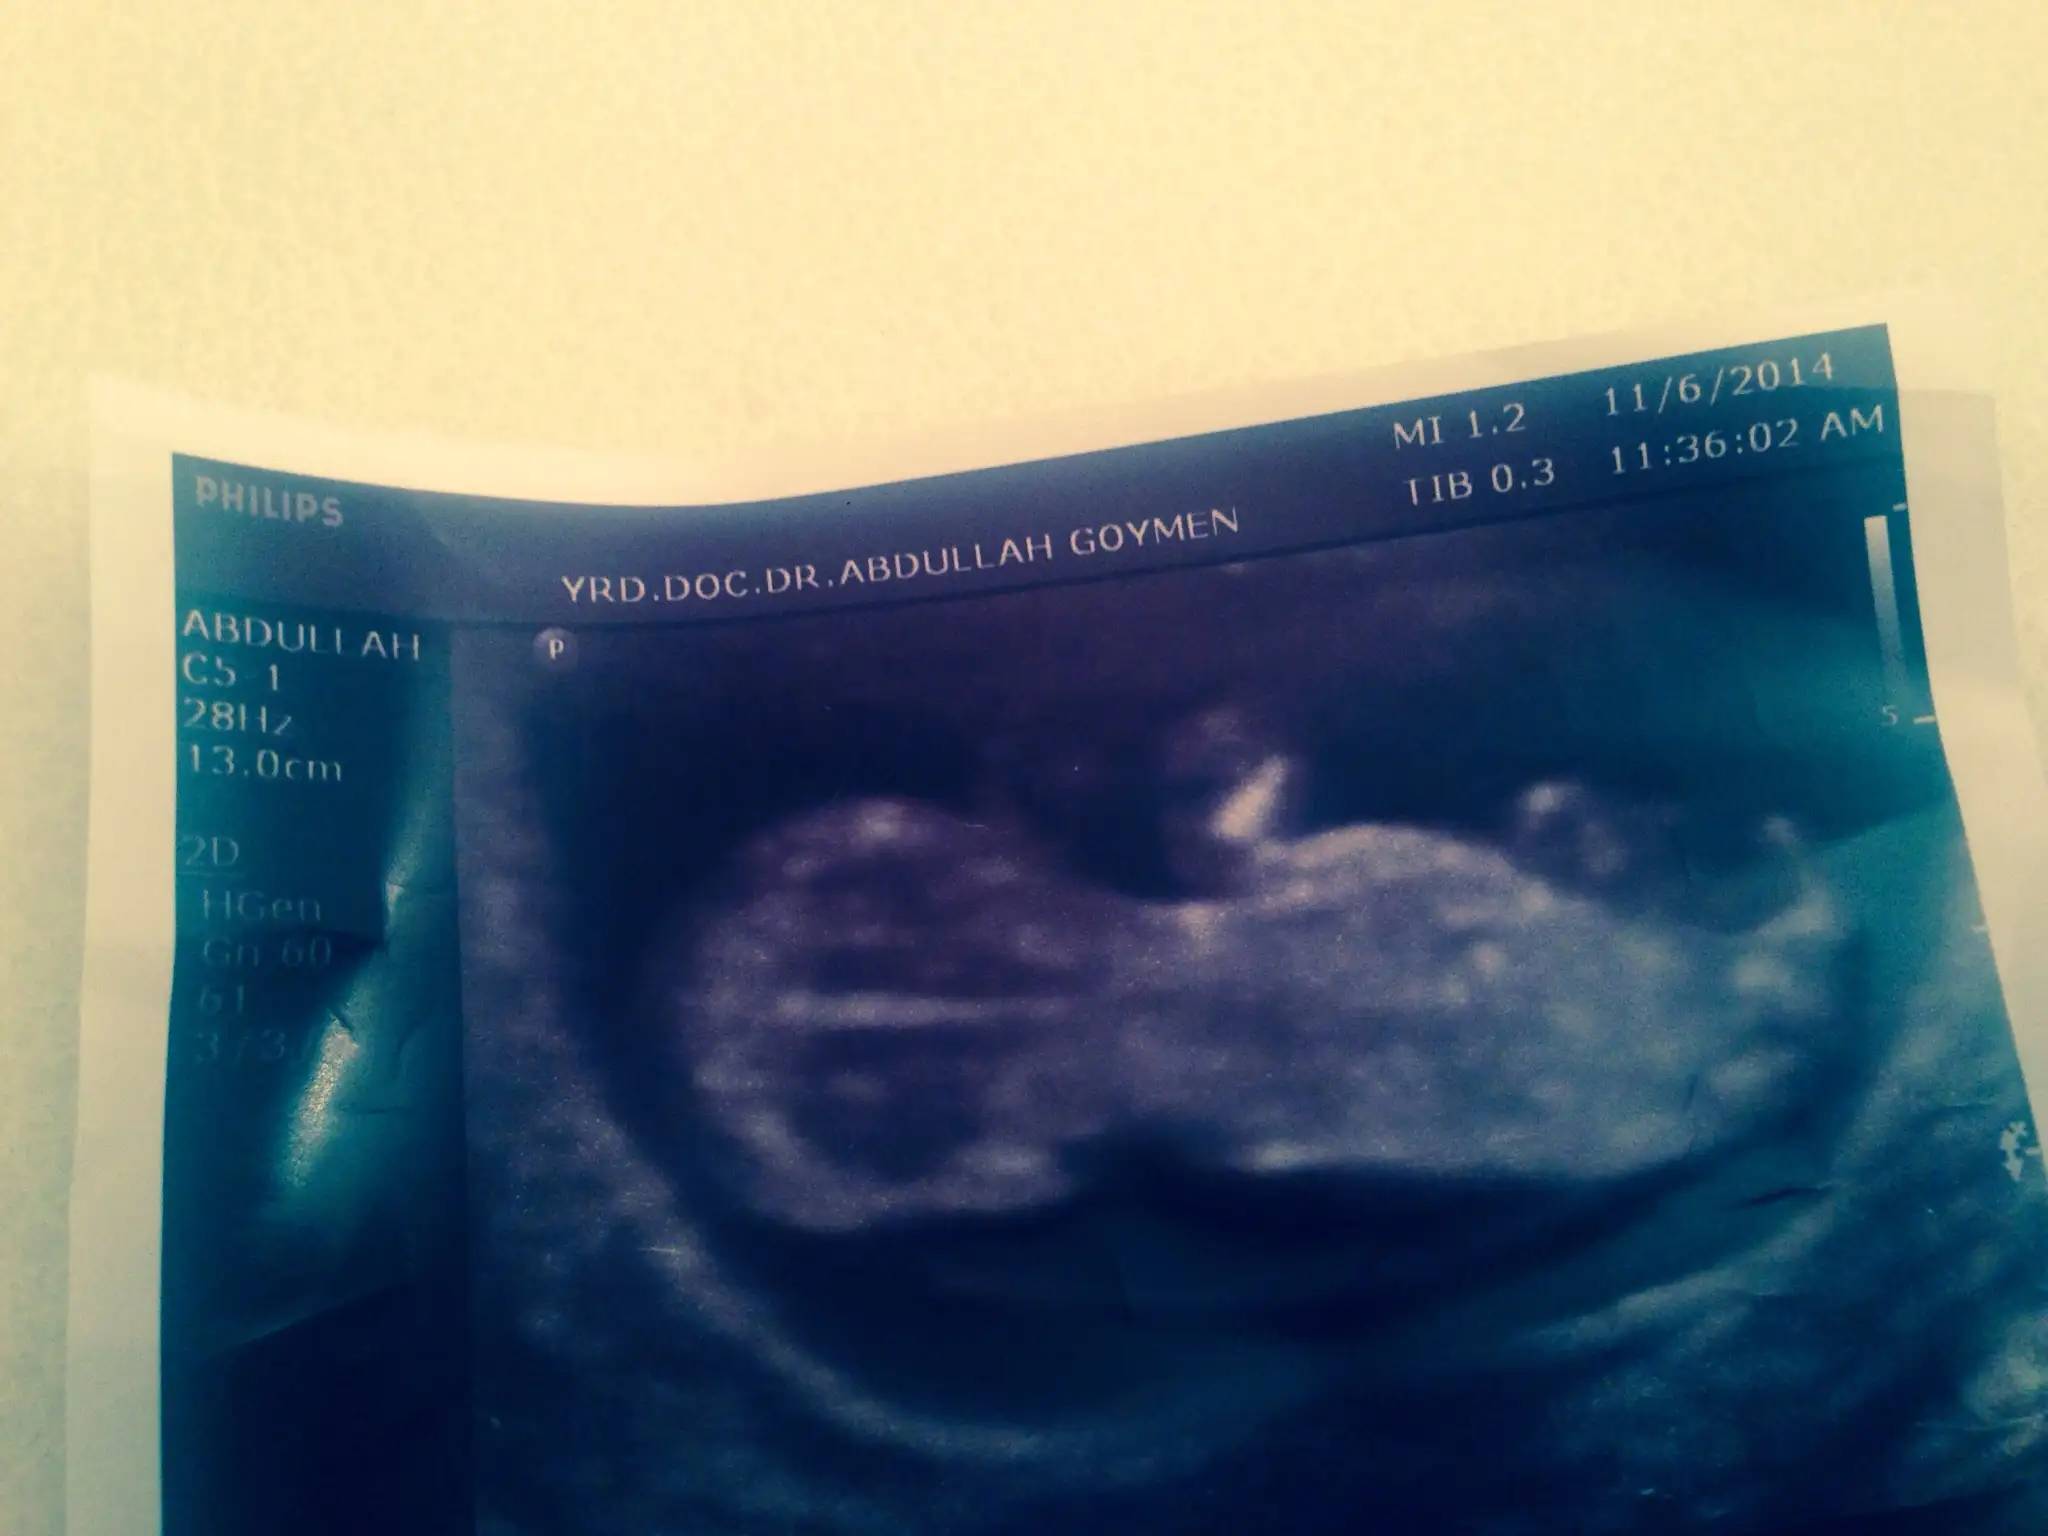

Bugun ayrintili ultrosonuma bakan dr.da kendini gostermiyo ama kiza benziyo sanki dedi. Gecen hafta dr.umda erkege benziyo demisti.hey allahim olucem meraktan.3 hafta daha beklicem simdi.bu resimlerdede belli olmuyo galiba???

oğlumun görüntüsüne benziyor erkek olabilir gibi geldi bana dr 11. haftada cinsiyeti %90 erkek dedi ve doğru çıktı sizde sorun biliyor ama demiyorlar :)